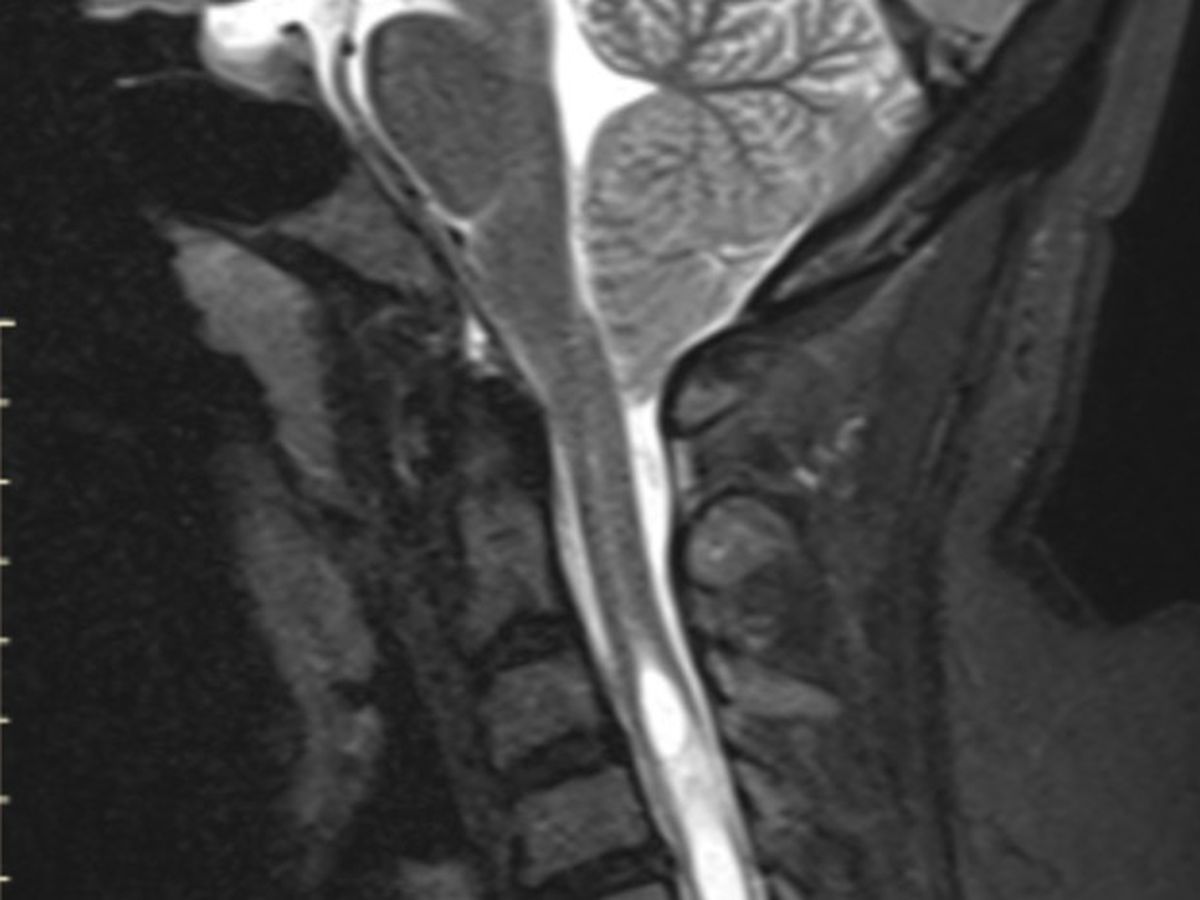

I’m Candice a 39 yr mom of two who started feeling sicker than my norm as someone who already has an auto immune disorder Im not new to feeling unwell. My bodily functions began to deteriorate slowly to the point where my grasp has faded in my hands, swallowing became difficult as well as holding my breath to even not be able to hold my urine. I went in for an MRI thinking it’s just sciatica in my neck. NOPE THAT WOULD'VE BEEN A BLESSING I GET THE RESULTS I HAVE WHATS CALLED A CHIARI MALFORMATION. Which most people who have the type that I have usually are born with from not developing properly as a fetus from a number of things in my case the drs believes it was from my mothers drug use. I now have to undergo a Chiari decompression surgery which is where the remove a section of the base of the skull and a piece of the spinal cord and this will require me to be out of work for at least 3 months. I’m not comfortable with putting this out here but it’s could use all the help I can get to make sure I don’t fall to behind on basic bills as well as extra bills now like laundry as I’m not allowed to lift anything or bend in half I also live on a 4th floor walk up so now I need someone to do this as well as buying my groceries and things like this. I have help but my family also can’t be here all the time. So I’m asking for any bit of help anyone can give even if it’s just a share. I want to say thank you ahead of time for anyone who helps out in anyway possible May you all be blessed.